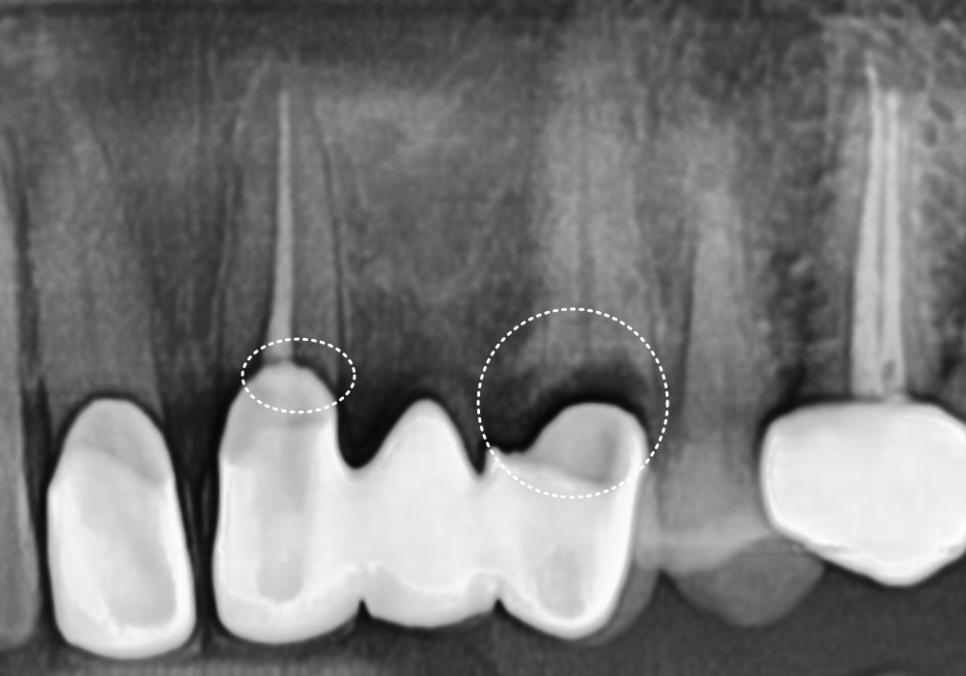

방사선 사진을 살펴보니 역시나,

2차 충치로 인해 치아 뿌리와 보철물 사이가

완전히 끊어져있네요.. ㅜㅜ